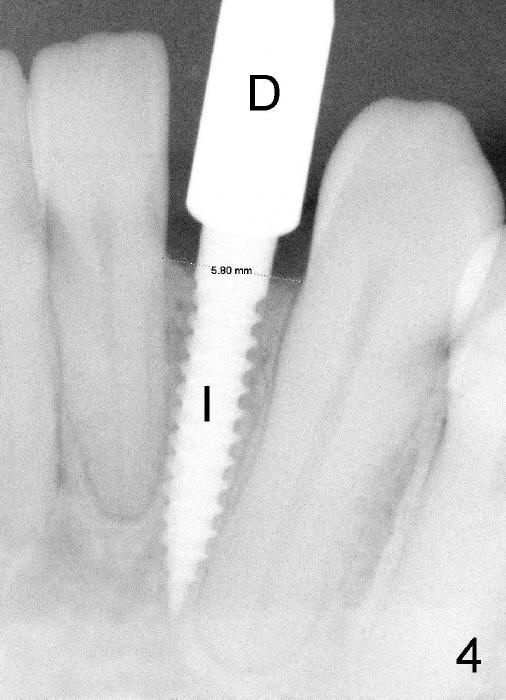

A 44-year-old phobic black lady requests implant restoration for #23, a congenital missing incisor (Fig.1).  The space between the roots of the neighboring teeth is 3.41 mm.  The smallest permanent implant is 3 mm in diameter.  She had ortho probably 20 years ago.  At first, diastemata among the lower anteriors were closed.  They relapsed.  Finally, a single edentulous space was created in hope to place an implant.  A retainer has been worn ever since. Her oral hygiene is poor, partially due to long term wearing of the retainer.  It appears that she cannot go back to the orthodontic office to redo ortho, most likely due to finance.

Informed consent is obtained with emphasis of potential damage to the neighboring roots.  Two PAs have to be taken with the first pilot drill (1.5 mm) in place for determination of initial trajectory (Fig.2,3).  Osteotomy is enlarged coronally with 2 mm pilot drill.  Finally a 3x17 mm one piece implant is placed with primary stability, determined tactilely (Fig.4).  Immediate provisional is fabricated.  To avoid micromovement, the immediate provisional (Fig.5 P) is bonded to the neighboring teeth with composite (*); it is further fixed in place with a lingual retainer (Fig.6 arrowhead).